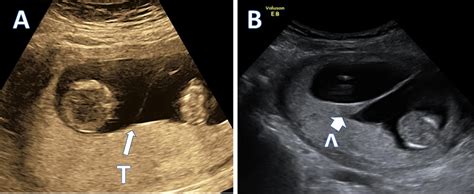

• lambda vs t sign twins